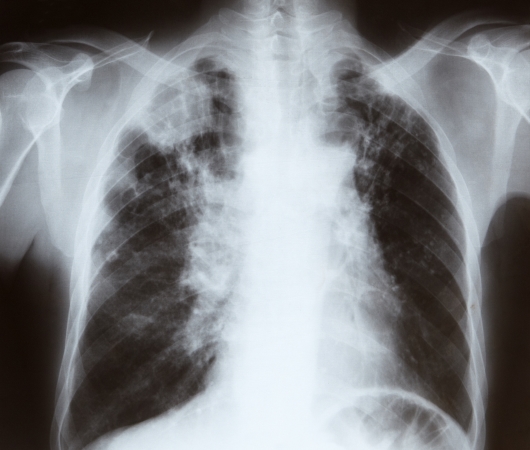

폐암은 국내 암 사망률 1위로, 과거에는 흡연이 폐암의 주요 원인이었지만 최근에는 비흡연자의 폐암 발병이 크게 증가하고 있습니다. 폐암은 오랜 기간 암 사망률 1위를 차지하고 있지만, 의학의 발전으로 생존율이 높아지고 있습니다. 그러나 초기 단계에서 올바르게 관리하는 것이 중요합니다. 폐암의 초기 징후가 무엇인지, 폐암에 좋은 음식은 무엇인지 알아두는 것이 좋습니다.